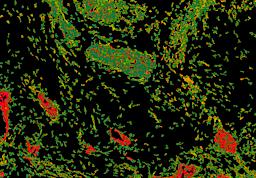

Pancreatic ductal adenocarcinoma is a lethal disease with limited treatment options and poor survival. We studied 83 spatial samples from 31 patients (11 treatment-naïve and 20 treated) using single-cell/nucleus RNA sequencing, bulk-proteogenomics, spatial transcriptomics and cellular imaging. Subpopulations of tumor cells exhibited signatures of proliferation, KRAS signaling, cell stress and epithelial-to-mesenchymal transition. Mapping mutations and copy number events distinguished tumor populations from normal and transitional cells, including acinar-to-ductal metaplasia and pancreatic intraepithelial neoplasia. Pathology-assisted deconvolution of spatial transcriptomic data identified tumor and transitional subpopulations with distinct histological features. We showed coordinated expression of TIGIT in exhausted and regulatory T cells and Nectin in tumor cells. Chemo-resistant samples contain a threefold enrichment of inflammatory cancer-associated fibroblasts that upregulate metallothioneins. Our study reveals a deeper understanding of the intricate substructure of pancreatic ductal adenocarcinoma tumors that could help improve therapy for patients with this disease.